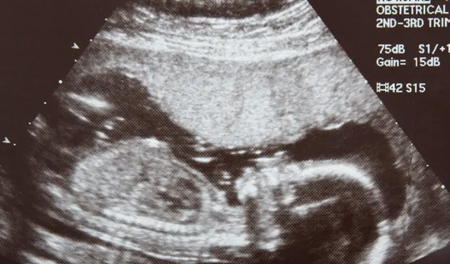

• Ultrasound (Sonography) – Real-time imaging using sound waves to examine soft tissues, internal organs, and vascular structures without radiation exposure.

• Obstetric & Fetal Ultrasound – Monitors pregnancy progress, fetal growth, and detects any developmental abnormalities early.

• Monitoring pregnancy or evaluating reproductive health

• Routine prenatal or preventive health screening